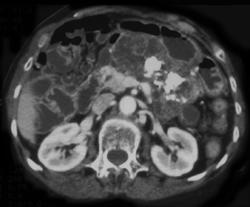

Diagnosis

Pancreatic Cancer